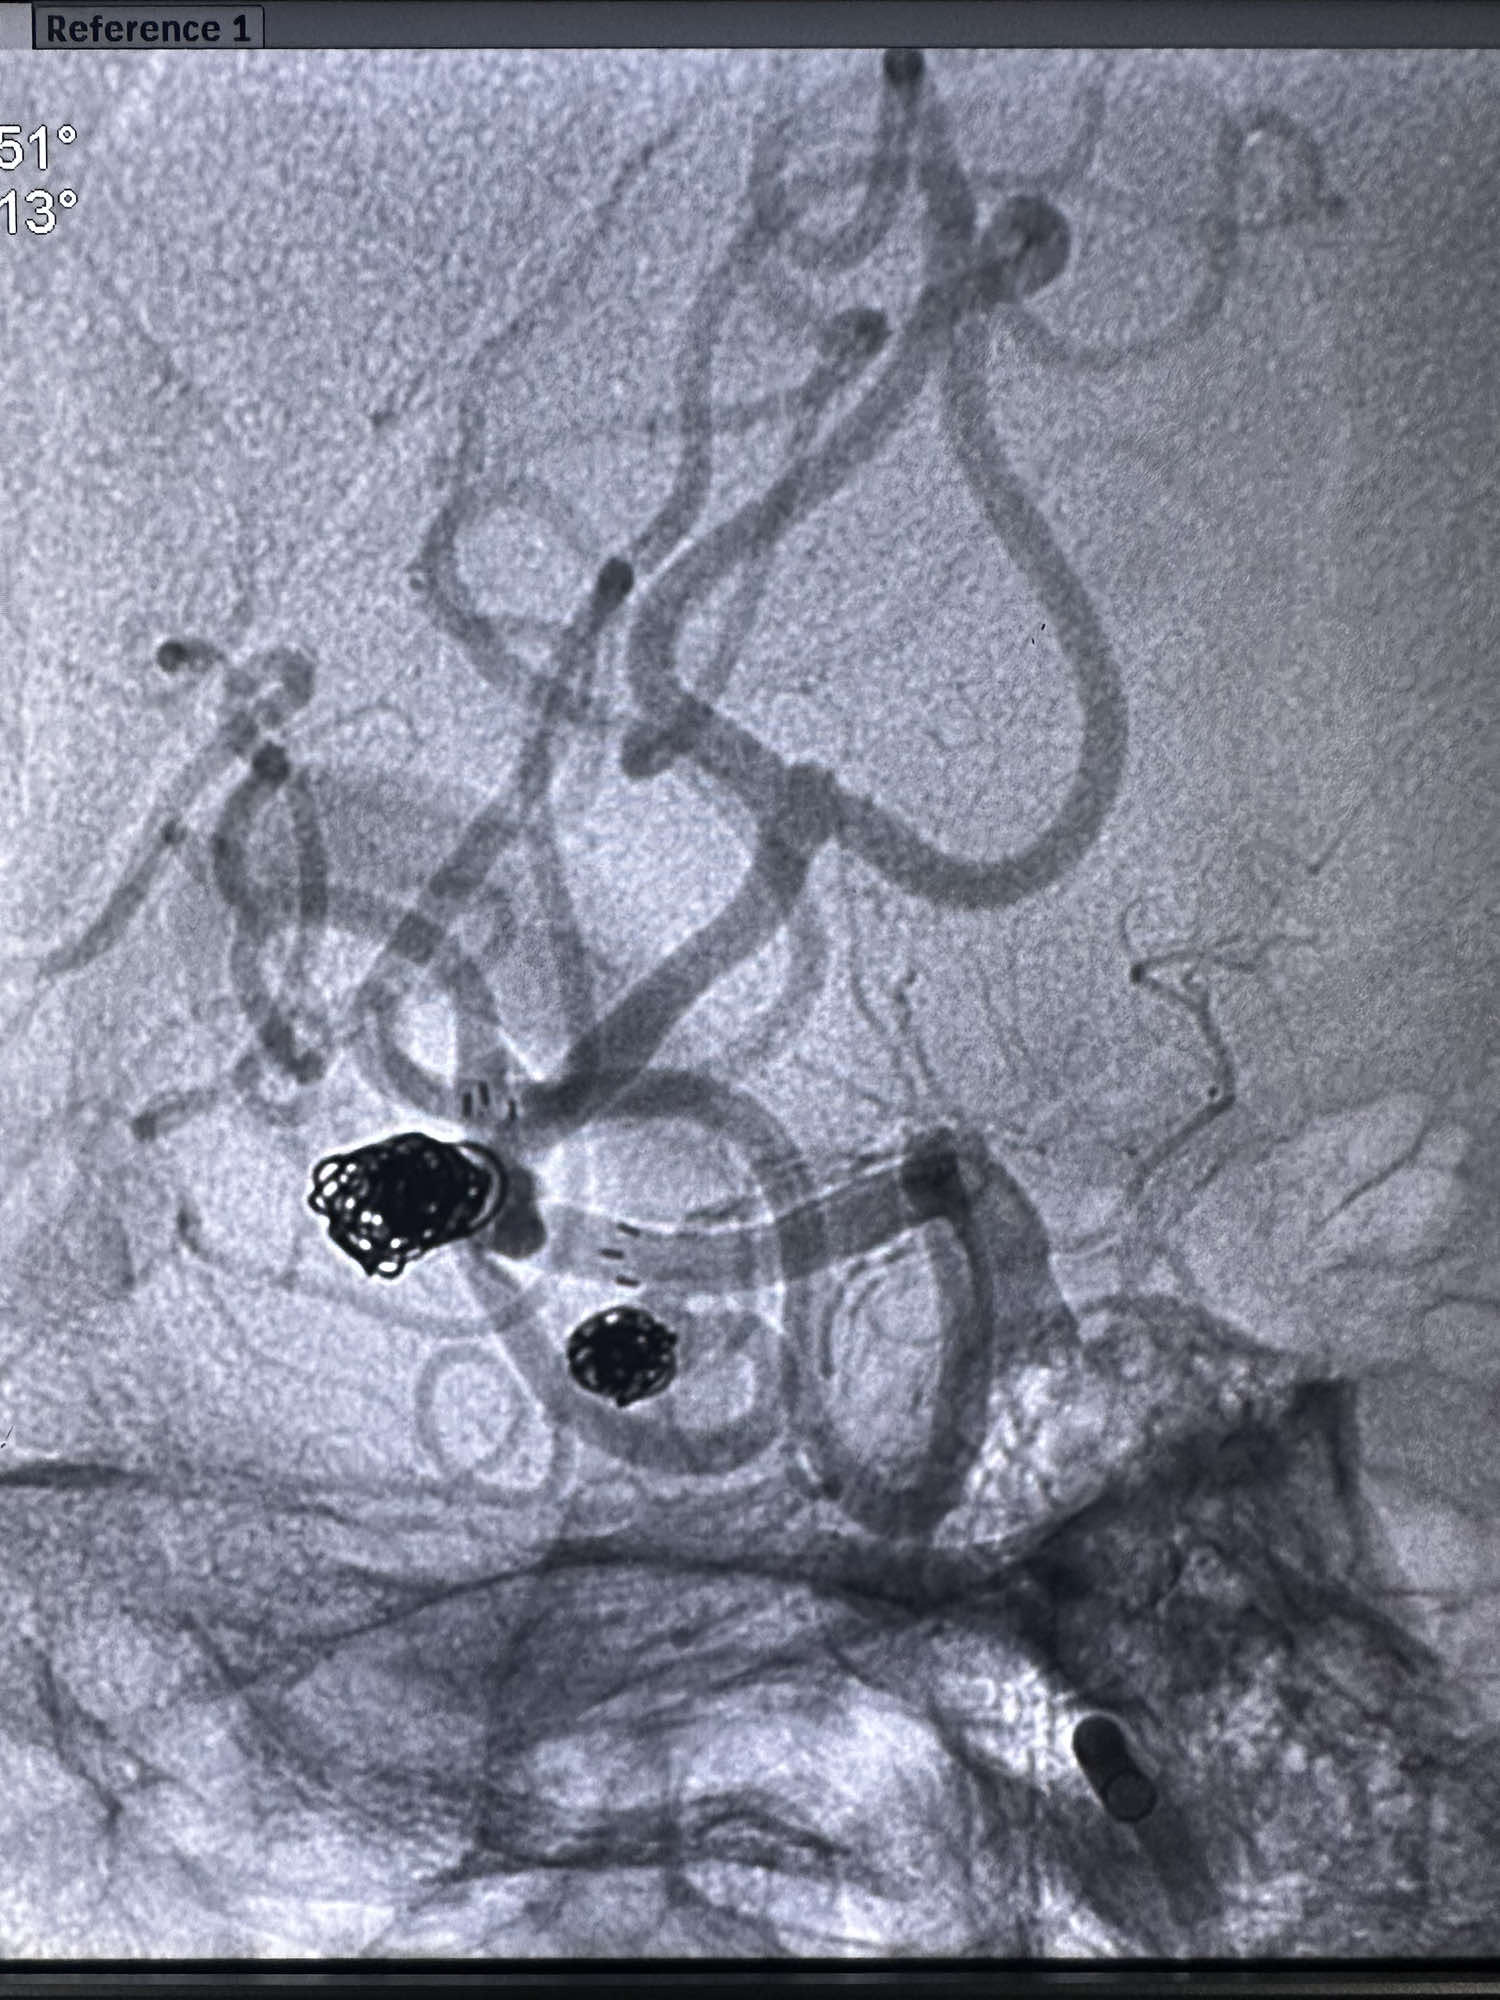

第一枚圈选择6的3D成篮圈,释放支架Atlas 3*15的支架,支架的远端放置在上干

第一枚圈的形态

后续填入多枚史赛克的弹簧圈

最后圈的形态